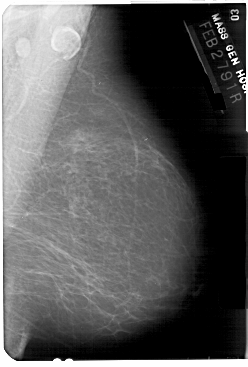

A_1375_1.LEFT_MLO

LEFT_MLO LINES 5491 PIXELS_PER_LINE 3601 BITS_PER_PIXEL 12 RESOLUTION 43.5 OVERLAY

FILE: A_1375_1.LEFT_MLO.OVERLAY

TOTAL_ABNORMALITIES 1

ABNORMALITY 1

LESION_TYPE MASS SHAPE OVAL MARGINS ILL_DEFINED

ASSESSMENT 4

SUBTLETY 4

PATHOLOGY BENIGN

TOTAL_OUTLINES 1

BOUNDARY